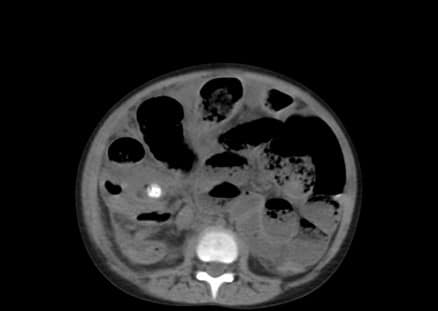

A plain CT of the abdomen was also taken to confirm the diagnosis before being taken to surgery. It showed dilated bowel loops, a radiopaque mass possibly fecalith or appendicolith, and an Inflamed and enlarged appendix. After taking the symptoms, signs, and investigations into consideration, the child was diagnosed with Appendicitis with small bowel obstruction and fecal impaction and taken to surgery. Figures 7 to 9 below show the CT images, axial section of the lower segment of the abdomen.

Figure 7: CT image of axial section of lower segment of abdomen showing dilated bowel loops

Figure 8: CT image showing radiopaque mass, possibly fecalith or appendicolith

Figure 9: CT image showing an inflamed and enlarged appendix with a possible faecolith or appendicolith